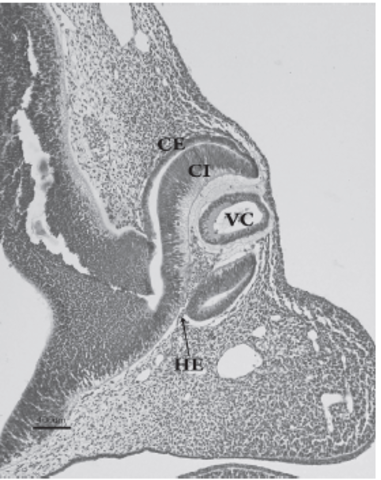

La vesícula óptica está relacionada con la formación de

la placoda cristaliniana. Ésta se invagina, constituyendo la vesícula cristaliniana. Al mismo tiempo, la porción distal e inferior de la vesícula óptica se deprime de forma gradual para formar una invaginación con dos capas, interna y externa, denominada cúpula óptica. Esta invaginación recorre longitudinalmente el pedículo óptico formando una hendidura conocida como hendidura

embrionaria

El iris se forma a partir del reborde de la cúpula óptica,

cubriendo parcialmente al cristalino. El epitelio iridiano

presenta las dos capas de la cúpula óptica; se continúa con el epitelio del cuerpo ciliar y con el epitelioretiniano pigmentario y sensorial.